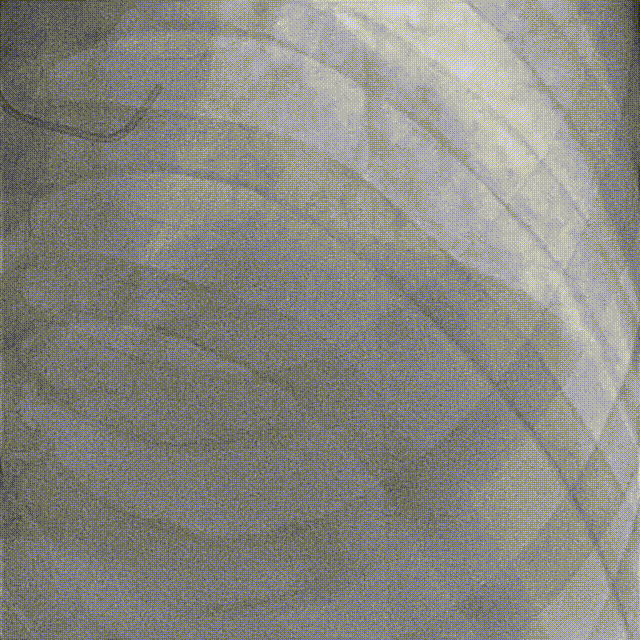

先后于3条分支球囊低压扩张,及冠脉内注入欣维宁。

再次沿PD导丝抽吸,注射器无明显回血,缓慢回拉退出抽吸导管,冲洗后未见明显血栓;但指引导管压力消失,心电正常。考虑血栓嵌顿于指引导管,尝试以注射器连接指引导管反复回抽后回血顺畅,抽出约3cm粗大血栓。

复查造影见右冠血流通畅,无明显残余狭窄及夹层影